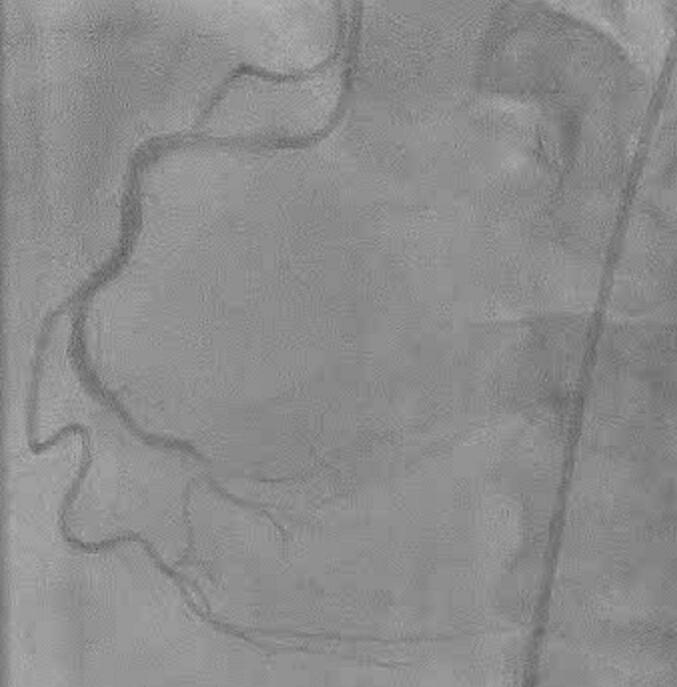

PRESENTATION OF CASE

This report describes our case of a 62-year-old male with PIVSD and cardiogenic shock. Impella was placed to ensure hemodynamic stability. Subsequently, right heart failure was suspected to be caused by insufficient circulatory support from Impella alone. Emergency surgery was considered, but it was high risk and only a few days had passed since the onset. Venoarterial extracorporeal membrane oxygenation (VA-ECMO) was implanted to treat right heart failure and delay surgical repair as long as possible. Six days after Impella implantation, the patient underwent a successful surgical repair via the right ventricle without associated adverse events.